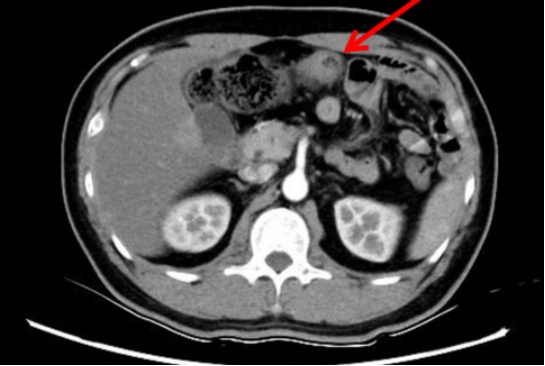

2024-10-10随访出现新发情况:肠镜发现横结肠腺癌(4cm×3cm)

·

进一步完善腹部增强CT提示横结肠病灶,肝肺均未提示转移。

2024-10-22腹腔镜扩大右半结肠癌根治术。

术后病理:腺癌,结合免疫组化及病史倾向胃腺癌浸润/转移,脉管内癌栓:(+);神经侵犯:(+);淋巴结转移情况 :总数:(0/13)无转移。